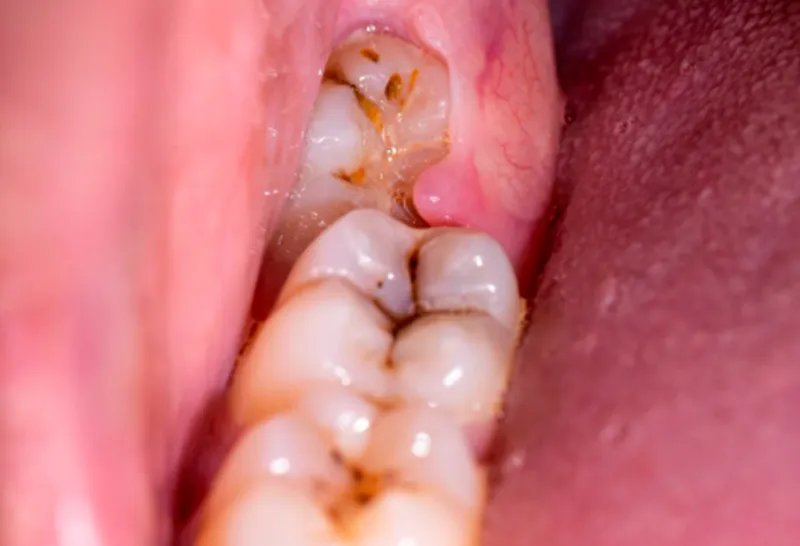

Exodontias simples e complexas (ênfase em terceiros molares)

Cirurgias complementares (pré-protética, biópsias, frenectomias, entre outras)

Complicações cirúrgicas e manejo de urgências em consultório odontológico